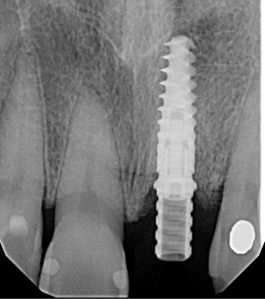

Preoperative 3D imaging is helpful in visualizing the patient’s anatomy and screening the ideal candidate. Since there is limited bone available, a dental implant with aggressive threading is important to obtain good primary stability. Typically, the socket is larger than the diameter of the dental implant and a bone graft is required to fill the space. A large stock, or customized healing abutment, can then be used to contain the bone graft and allow for ideal soft tissue healing.